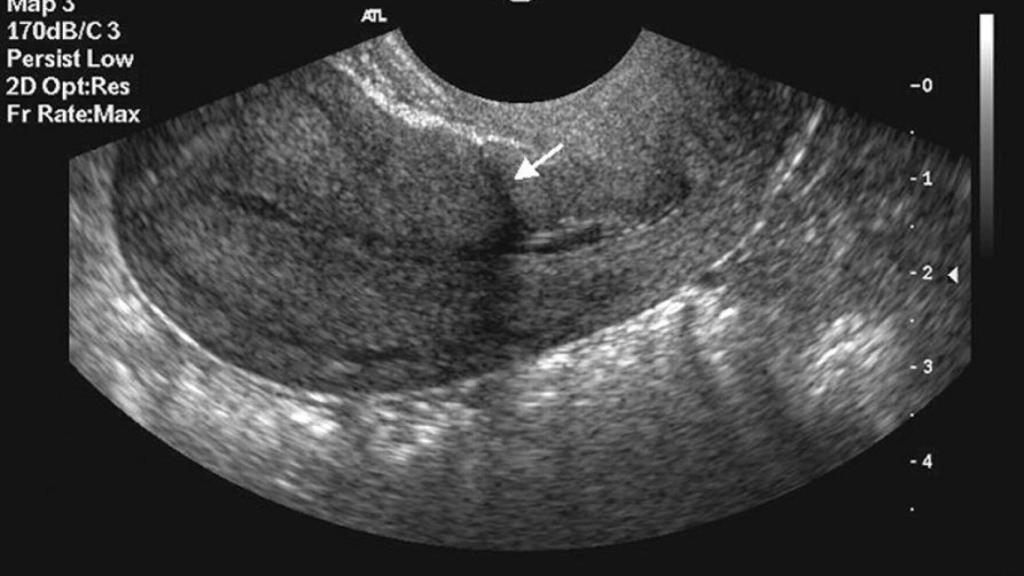

Finalmente, tras realizarle una de las ecografías típicas del seguimiento de un embarazo, los médicos detectaron que el saco gestacional se encontraba en la parte inferior del útero, cercano a una antigua cicatriz de cesárea. Asimismo, la bolsa que contenía el feto y el líquido amniótico tenía más vasos sanguíneos a su alrededor de lo normal, un signo de sospecha de CSP.

Aunque la mujer decidió continuar con el embarazo siguiendo un control muy riguroso, las ecografías realizadas cada dos o cuatro semanas acabaron evidenciando el desarrollo de una placenta retenida, la cual además se situó a lo largo del cuello del útero de la mujer, una condición denominada "placenta previa"y la cual implica que la misma placenta obstruiría el canal uterino complicando un parto vaginal.